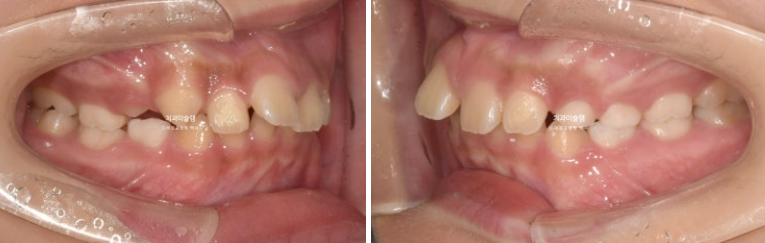

윗니 돌출이 측면에서 잘 보이네요.

영구치날 공간은 비교적 양호한 편입니다.

파란화살표 자리에 있어야할 작은어금니가 선천적 결손 상태입니다.

이런 경우 계승영구치가 없어 오래도록 남아있게될 잔존유치를 최대한 보존해서 쓰는 방법으로 치료를 합니다.